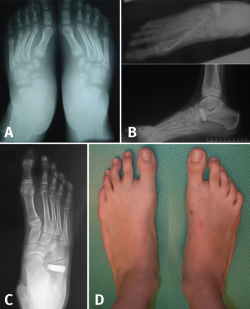

El pie en serpentina o en Z constituye una deformidad rara en el pie, que combina valgo del retropié con aducción del antepié (Figura 18).

Figura 18. Pies en serpentina. A: radiografía dorsoplantar de la deformidad en serpentina; B: imágenes radiológicas postoperatorias inmediatas, donde se aprecia osteotomía de Mosca y técnica de Cahuzac percutánea; C y D: imagen clínica y radiológica un año tras la intervención.

A menudo infradiagnosticado, suele presentarse como un metatarso aducto resistente al tratamiento. En la radiografía se manifiesta con signos de valgo del retropié con divergencia AC aumentada y aducción del antepié al nivel de la articulación de Lisfranc.

En caso de indicación quirúrgica se debe corregir el doble componente de la Z con osteotomía de alargamiento de la columna externa (para corregir el valgo) más corrección del antepié mediante técnica de Cahuzac (apertura de la cápsula C1M y osteotomía de los metatarsianos centrales) modificada en percutánea(20).